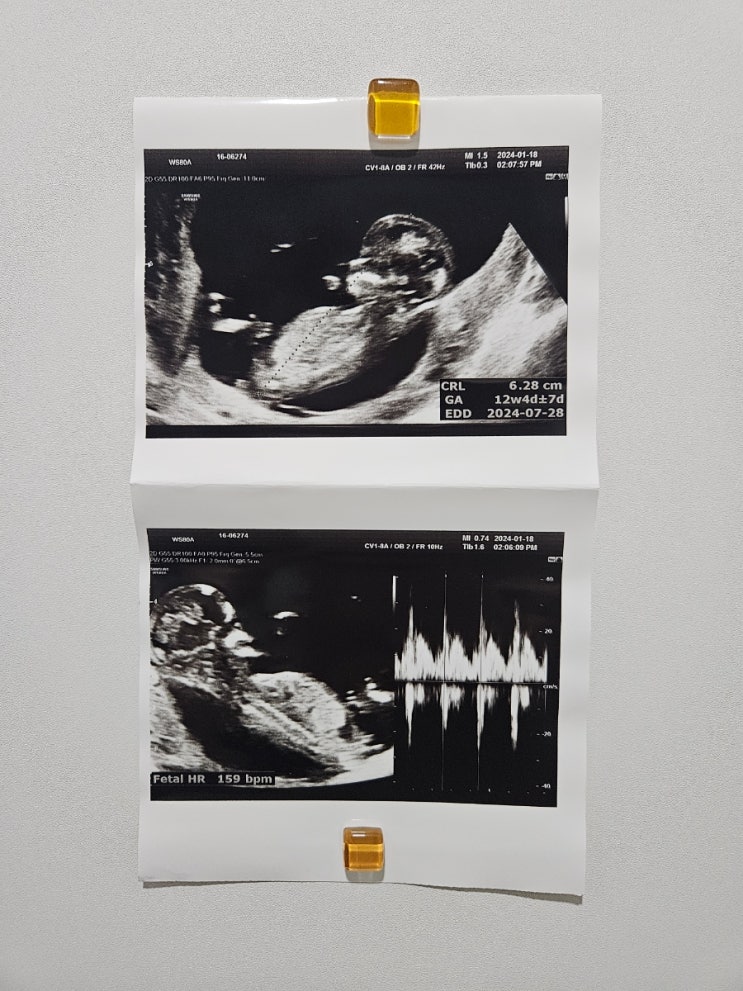

임신중기 12주-20주 1,2차 기형아검사 정밀초음파

12주1차기형아검사 NT - 목두께 검사 , 혈액검사 를 끝내고 다음진료 16주에 방문해서 2차기형아검사 혈...